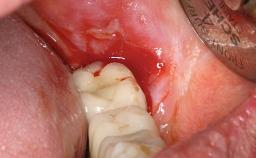

A 27-year-old male was referred to the periodontist for assessment and management of implant site 41. The implant had been placed nine years previously and restored with a screw-retained single crown. The patient was a cigarette smoker in good general health. He reported he had reduced his smoking habit from 25 cigarettes per day to 15 cigarettes per day in the previous six months. On examination, there was calculus and plaque present at the lower anterior teeth and at implant site 41. Localized attachment loss was observed at teeth 32 and 42, with 2–3 mm of gingival recession. At implant site 41, there were 8–9 mm probing depths with suppuration and bleeding on probing.